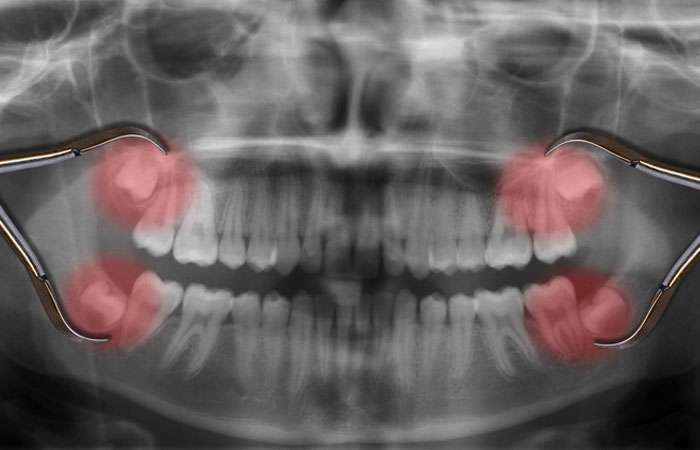

Even though impacted wisdom teeth are not visible in the mouth they can cause a number of problems. Commonly, patients will go to their dentist because of pain in the back of the jaws. Removal of the offending impacted tooth or teeth usually resolves the problem.

The impacted wisdom tooth itself may be the source of the pain or there may be an infection associated it. Bacteria that are always present in the mouth, can work their way down under the gum tissue and cause a painful infection around the crown of the wisdom tooth even though you can’t see the tooth. People often mistake repeated soreness of the gum tissue overlying the wisdom teeth as an effort by the teeth to erupt. Unfortunately this is often a warning sign that trouble is brewing. If this situations goes untreated for an extended period of time (removal of the impacted tooth), the infection may become chronic and lead to destruction of bone around the impacted tooth (a condition known as periodontal disease).

This bone destruction can extend around the other teeth in the back of the mouth and lead to future tooth loss! The same types of bacteria that are responsible for infections can also cause tooth decay or cavities on the roots of the other molar teeth. Just the constant pressure from the impacted wisdom tooth can lead to destruction of the tooth or teeth adjacent to it. Although the overall occurrence of cysts and tumors associated with the jaws is low, when they do occur it is most frequently around an impacted wisdom tooth.

The orthodontist may request that wisdom teeth be removal prior to braces as they may interfere with straightening the other teeth. Finally, an impacted wisdom tooth in the lower jaw occupies space that is usually filled by bone. This creates an inherent area of weakness in the lower jaw which may render it more susceptible to fractures (broken jaw).